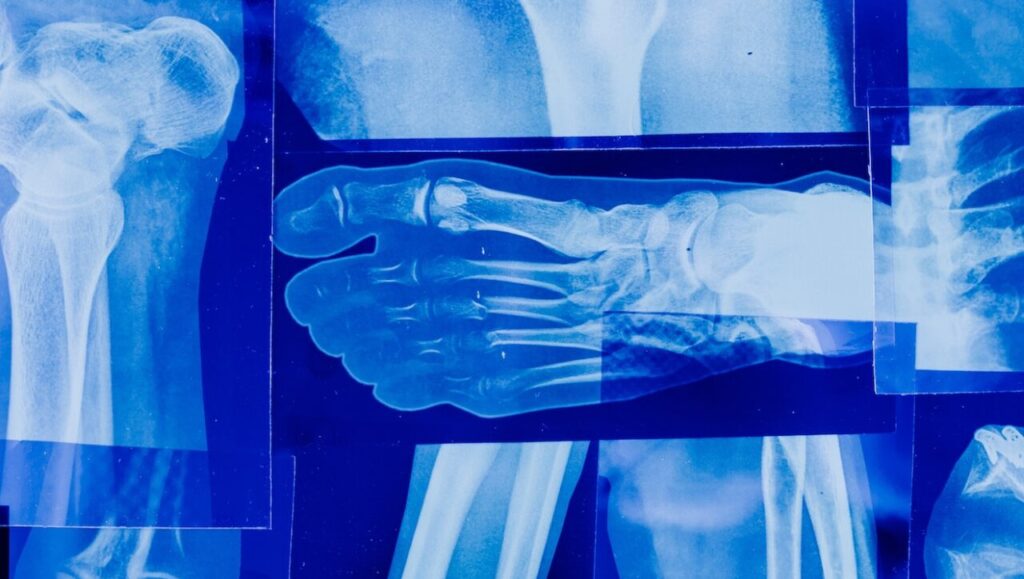

Radiografia

Cos’è? Una radiografia è un tipo di imaging medico che utilizza raggi X per creare immagini di strutture all’interno del corpo, come ossa, organi e